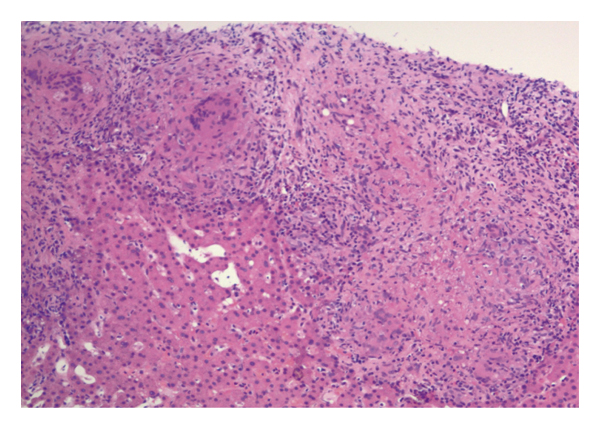

The patient was started on normal saline continuous infusion. Nephrology and oncology were consulted. The patient’s calcium level had normalized on day 2 of hospitalization. She eventually underwent a core needle biopsy of the left thyroid nodule which revealed granulomatous infiltration of the gland consistent with sarcoidosis (Figure 4).

Thyroid sarcoidosis is diagnosed with fine needle aspiration (FNA) biopsy or thyroidectomy for treatment of goiter demonstrating noncaseating epithelioid granulomas [9]. The false-negative rate of a benign interpretation is 0 to 3 percent [10]. In a retrospective study of nodules with two or more prior nondiagnostic FNAs, core needle biopsy was diagnostic in 86 compared with 29 percent for repeat FNA [11]. Core needle biopsy has low nondiagnostic result rates and high specificity for the diagnosis of malignancy. It is a safe diagnostic technique with a higher diagnostic yield, especially when molecular testing is not available or fine needle aspiration does not yield enough cells for molecular testing [12]. Our patient underwent an initial FNA with a marginally adequate cellularity; thus, a definitive diagnosis could not be obtained. A repeat FNA was warranted but given the higher specificity and sensitivity of the core needle biopsy compared to a repeat FNA; our patient underwent a core needle biopsy. The procedure revealed the final diagnosis.